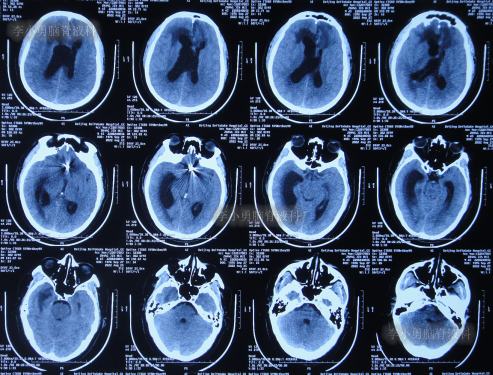

该院治疗20余天时间内,虽每天进行腰穿治疗,但期间3次查头颅CT均显示脑室持续的扩张(图-7、图-8、图-9)。

图-7:2022年8月9日头颅CT

图-8:2022年8月14日头颅CT

图-9:2022年8月15日头颅CT